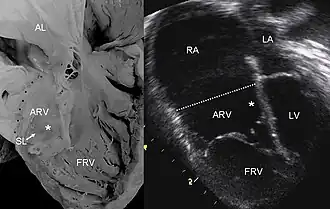

УЗИ изображение патологического состояние сердца при Аномалии Эбштейна. | |

Эхокардиографическое исследование. Отмечаются деформация эхосигнала от створок и объемное увеличение размеров правого предсердия.